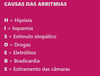

CAUSAS DE ARRITMIAS